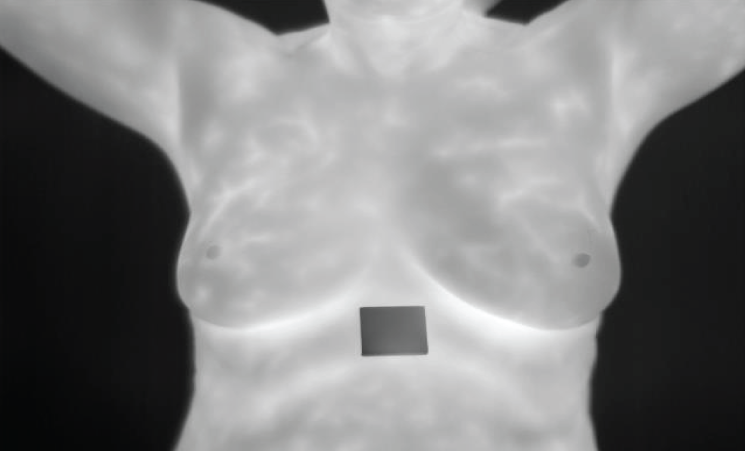

The dataset provided the image in Fig. 7. Thermographic images display body heat patterns that could imply cancer by revealing places where blood flow and metabolism increase due to malignancy. This picture acts as the starting point for any further processing or analysis.

Figure 7: Input sample thermograph

For standardizing input size during subsequent stages, the original thermograph was presented in Fig. 8 resized. Such rescaling is important to image analyzing particularly deep learning models which need constant input dimensions. Every image must be uniformly processed through resizing so that they can easily be handled and kept consistent with one another.

Figure 8: Resized image